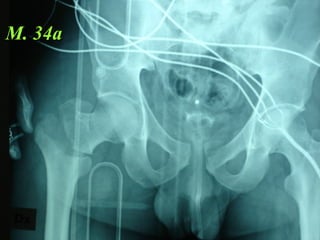

M. 34a

La lesione dell’apparato muscolo scheletrico che richiede  in ogni caso  un trattamento chirurgico con  priorità   assoluta  è la rottura dell’anello pelvico , che comporta una emorragia severa nel retro peritoneo e nella cavità peritoneale.

Immediata riduzione e fissazione del bacino

Se la risposta emodinamica a questo trattamento è buona il paziente verrà monitorato e potrà essere programmato un successivo intervento di osteosintesi definitiva

Angiografia e/o packing pelvico Se il paziente rimane instabile